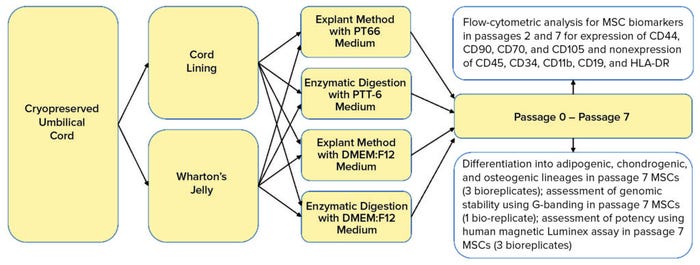

Here, we define and compare MSCs isolated from two main UC regions: the CL and WJ. We used cryopreserved UC tissues to verify that extracted MSCs are viable after cryopreservation (postthaw). Consequently, we determine whether the PTT-6 culture medium would alter characteristics of UC-MSCs after repeated passaging and culturing. We also investigate the extraction efficiency of two methods coupled with the two culture media used to isolate MSC populations from CL and WJ thawed after cryopreservation in UC tissue (Figure 1).

Figure 1: Umbilical cord lining and Wharton’s jelly were separated carefully from cryopreserved umbilical cord soaked in wash buffer. Tissues were explanted or digested and cultured in either PTT-6 medium or DMEM:F12 medium for six passages. Some cells were frozen at passages 1 and 6 for flow-cytometric analysis; others were assessed at passage 7 for genomic stability and therapeutic potential using differentiation assays, G-banding, and a human magnetic Luminex assay.